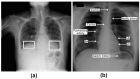

Pneumonia is responsible for high infant morbidity and mortality. This disease affects the small air sacs (alveoli) in the lung and requires prompt diagnosis and appropriate treatment. Chest X-rays are one of the most common tests used to detect pneumonia. In this work, we propose a real-time Internet of Things (IoT) system to detect pneumonia in chest X-ray images. The dataset used has 6000 chest X-ray images of children, and three medical specialists performed the validations. In this work, twelve different architectures of Convolutional Neural Networks (CNNs) trained on ImageNet were adapted to operate as the resource extractors. Subsequently, the CNNs were combined with consolidated learning methods, such as k-Nearest Neighbor (kNN), Naive Bayes, Random Forest, Multilayer Perceptron (MLP), and Support Vector Machine (SVM). The results showed that the VGG19 architecture with the SVM classifier using the RBF kernel was the best model to detect pneumonia in these chest radiographs. This combination reached 96.47%, 96.46%, and 96.46% for Accuracy, F1 score, and Precision values, respectively. Compared to other works in the literature, the proposed approach had better results for the metrics used. These results show that this approach for the detection of pneumonia in children using a real-time IoT system is efficient and is, therefore, a potential tool to aid in medical diagnoses. This approach will allow specialists to obtain faster and more accurate results and thus provide the appropriate treatment.